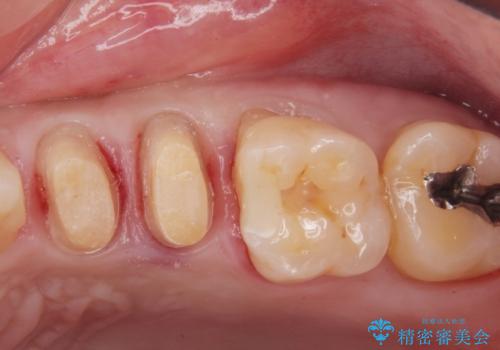

- 銀歯を白くしたい。水が少し染みるとの事で来院。

歯と歯茎の境目にプラスチック樹脂の治療の後があり、そこが染みる原因となっていました。

拡大鏡下で銀の詰め物、古いプラスチックの樹脂を外し、虫歯が残ってないかを確認して

ジルコニアクラウンで治療を行いました。